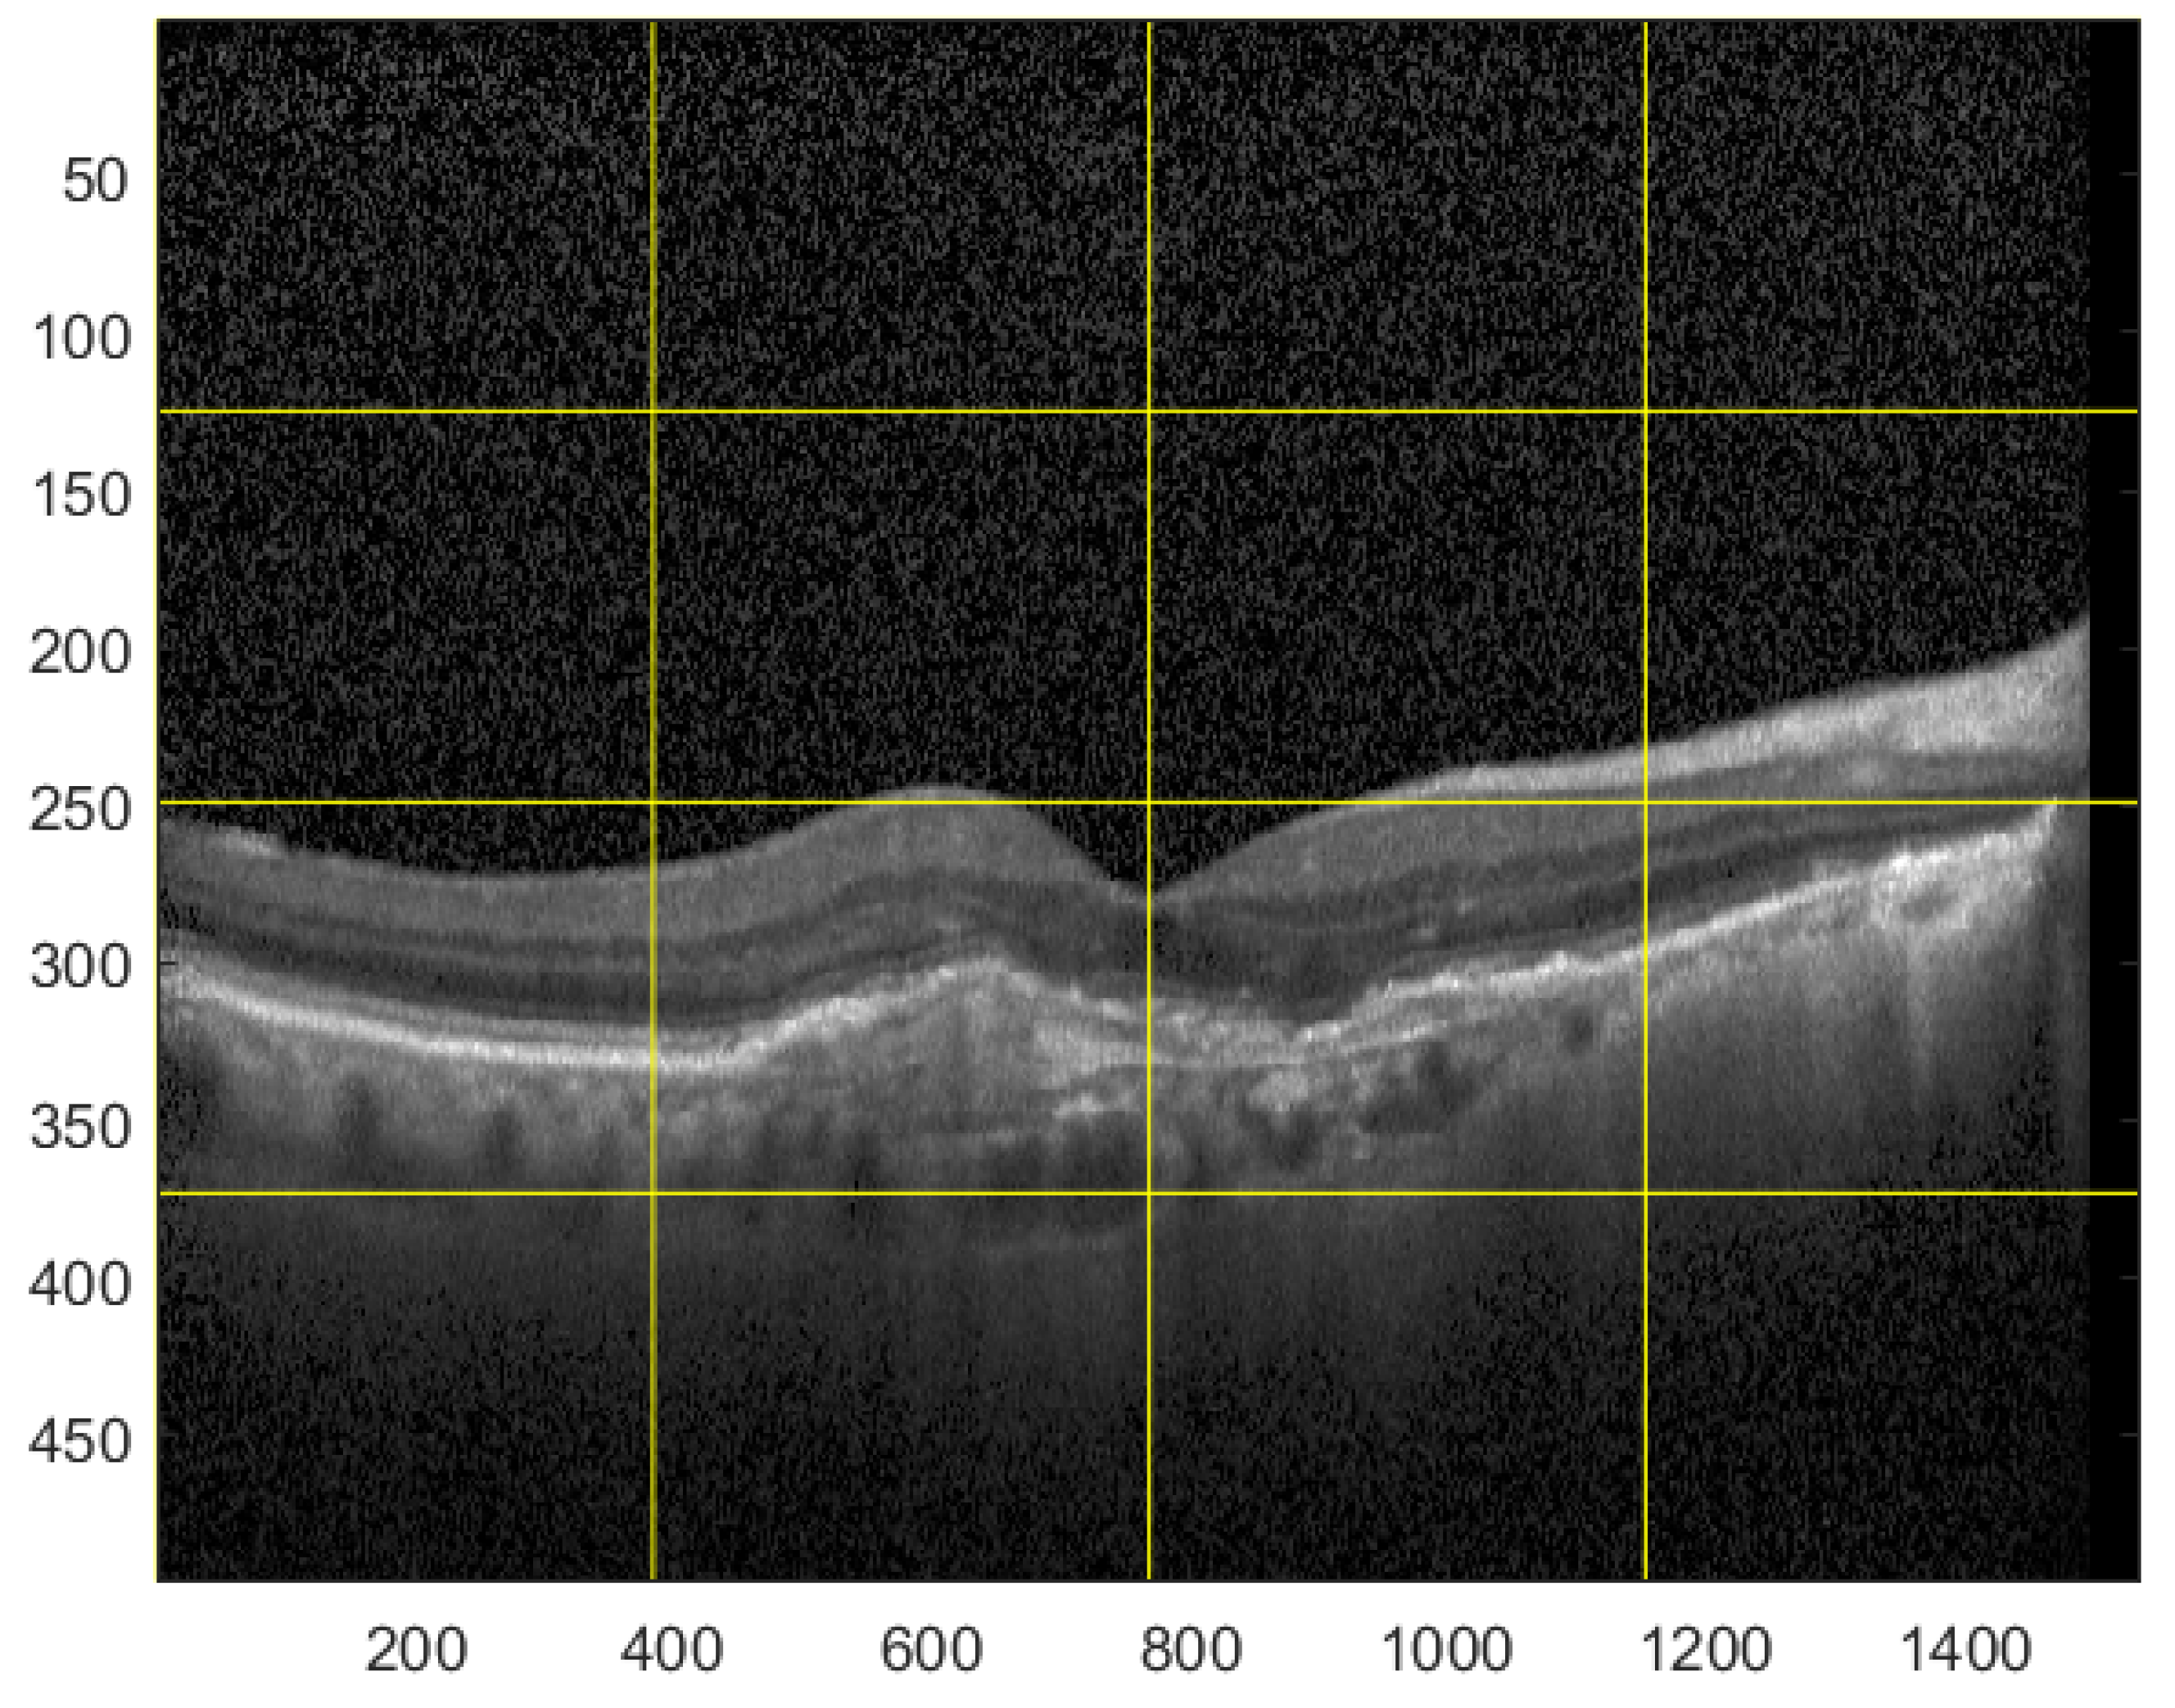

- a.